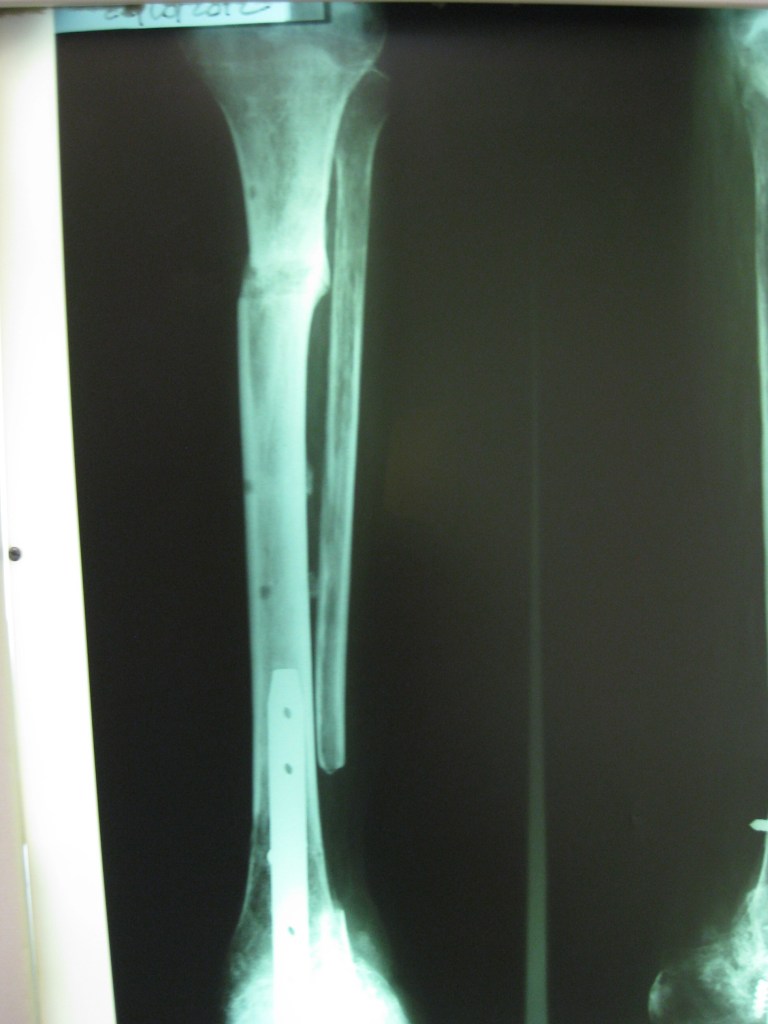

Mensaje de Agradecimiento

tras múltiples cirugías y una osteomielitis grave en mi pierna , la única opción que me daban era la amputación con desarticulación , fue mi hermana quien consulto en Cotram con el Dr Dratewka quien me propuso un tratamiento para tratar la infección y al mismo tiempo reconstruir mi hueso faltante

Tras dos años puedo decir que valió la pena el esfuerzo